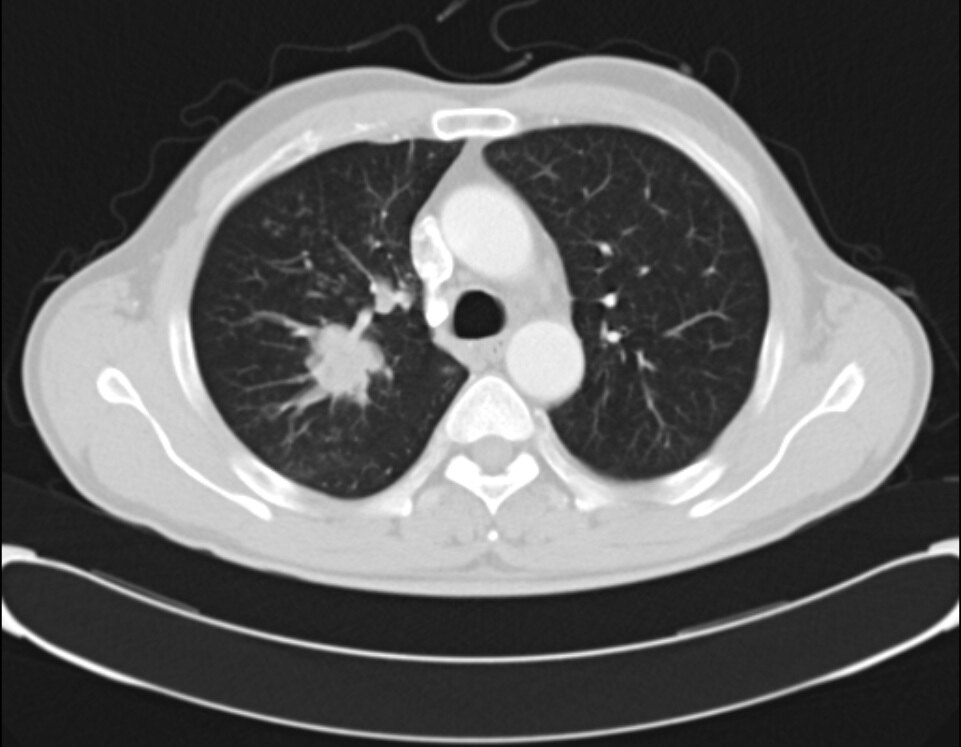

目前,低剂量螺旋 CT 是肺癌筛查的主要手段之一,它能够清晰地检测出肺部的小结节和早期病变,相较于传统的胸部 X 光检查,具有更高的灵敏度和准确性。根据美国国家综合癌症网络(NCCN)的指南建议,肺癌高危人群应每年进行肺部低剂量螺旋 CT 检查。具体来说,55 - 74 岁,正在吸烟或者戒烟少于 15 年,并且吸烟指数大于 30 包年(600 年支)的人群;以及年龄大于 50 岁,吸烟指数大于 20 包年(400 年支),并且合并肿瘤病史、肺病史、家族中有肺癌患者、氡暴露和致癌物质的职业性暴露等情况之一者,都应重视定期筛查,积极采取预防措施,将肺癌的风险降到更低。